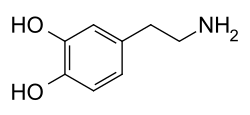

Dopamina

| Nome IUPAC | 3,4-dihidroxi-feniletanamina | ||||||||||||||

| Outros nomes | 2-(3,4-dihidroxifenil)etilamina; 3,4-dihidroxifenetilamina; 3-hidroxitiramina; DA; Intropina Revivan; Oxitiramina | ||||||||||||||

A dopamina (DA, uma contração de 3,4-di-hidroxifenetilamina) é um neurotransmissor monoaminérgico, da família das catecolaminas e das feniletilaminas que desempenha vários papéis importantes no cérebro e no organismo. Os receptores de dopamina são subdivididos em [[Receptor D1 de dopamina|D1], D22, D3, D4 e D5, de acordo com localização no cérebro e função. O cérebro contém várias vias dopaminérgicas, como a via mesolímbica, que desempenha um papel importante no sistema de comportamento motivado a recompensa.[3] [4] A maioria das recompensas aumentam o nível de dopamina no cérebro, e muitas drogas viciantes aumentam a atividade neuronal da dopamina. A dopamina é produzida especialmente pela substância negra e na área tegmental ventral (ATV). A dopamina também está envolvida no controle de movimentos, aprendizado, humor, emoções, cognição e memória.[5]